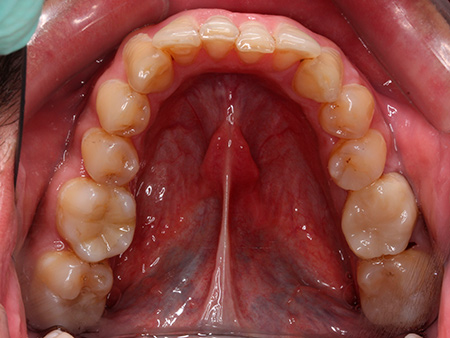

José ya había finalizado un tratamiento de ortodoncia con brackets metálicos antes de acudir a Ferrus & Bratos. Sin embargo, no había utilizado retenedores, por lo que los dientes habían vuelto a moverse con el paso de los años. Por ello, tenía mucho interés en conseguir una sonrisa alineada y funcional.

Por su trabajo, José viaja mucho y en ocasiones pasa más de un mes fuera de casa, por lo que la doctora Patricia Bratos le recomendó la ortodoncia con Invisalign, pues las revisiones en este caso son cada 4 o 6 semanas. Después de una ortodoncia de 24 meses de duración, nuestro paciente está encantado con el resultado y también con el trato recibido.